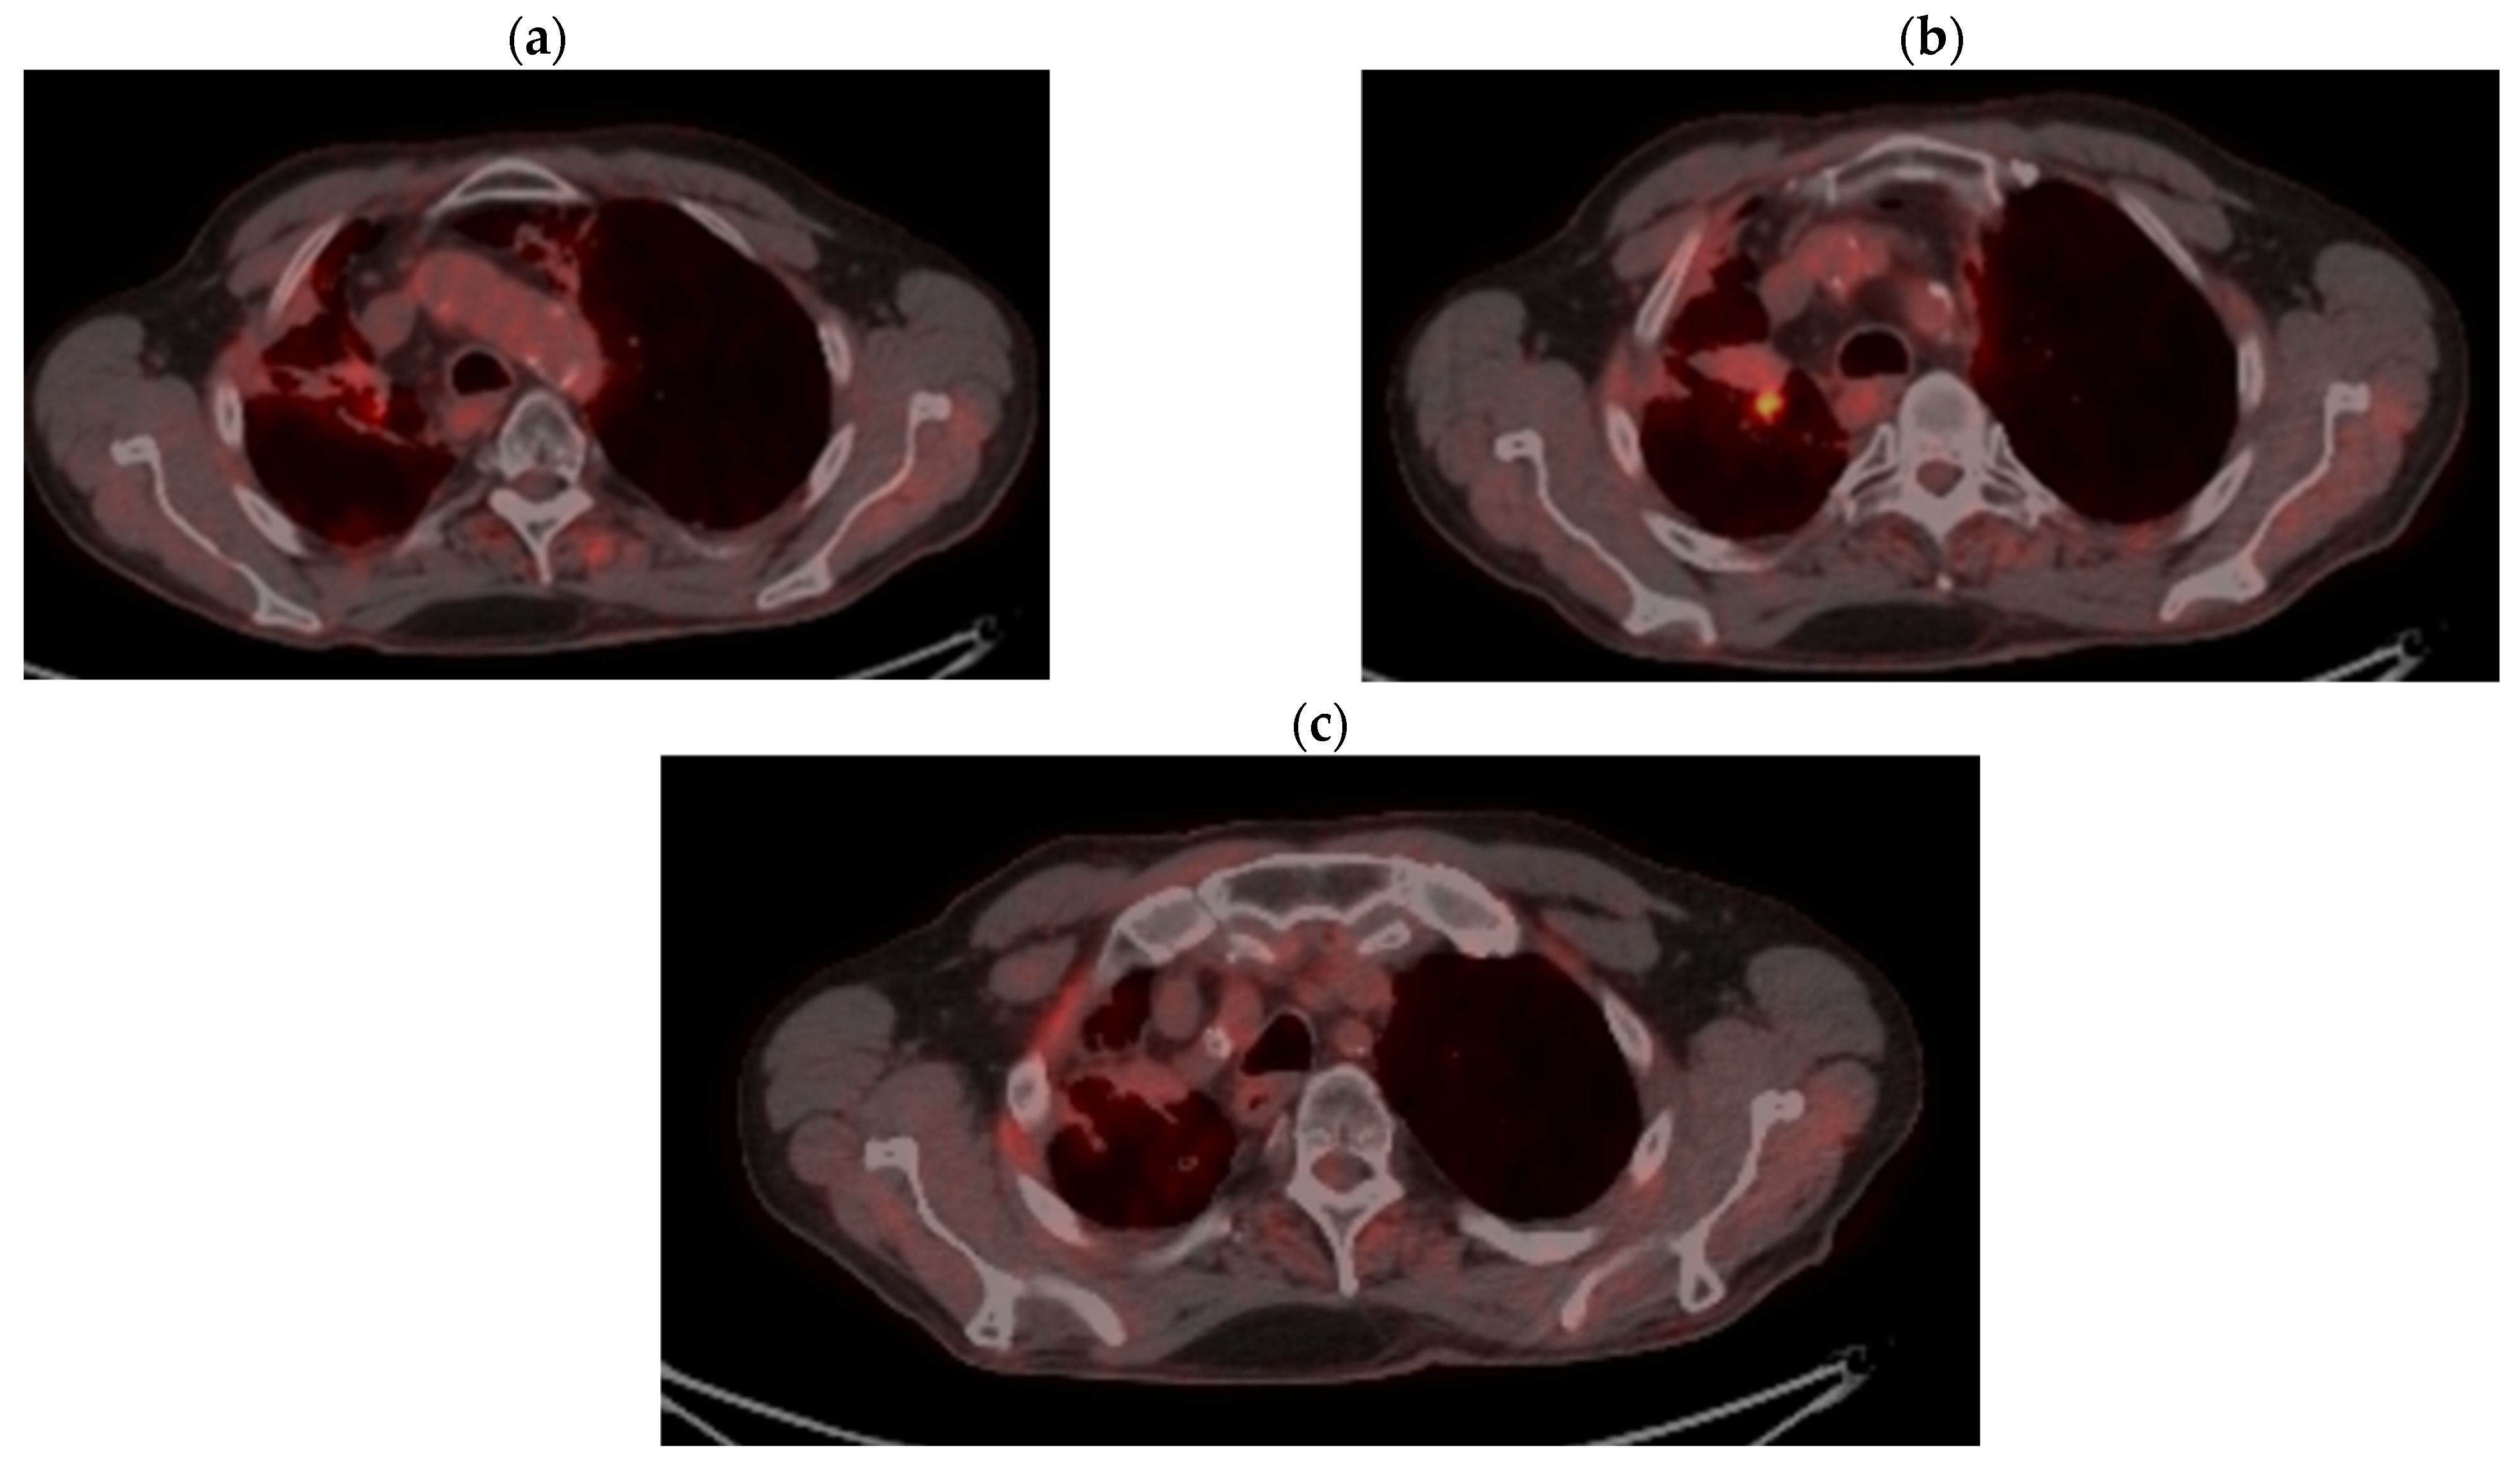

2. Case Presentation

2.2. Monitoring 2022: Oncological Commission 1910/16.08.2022

2.3. Oncological Committee 07/25/2023 Recommended

- Consider rescue re-irradiation (SBRT), taking into account the current primary tumor dimensions of 24 × 34.2 mm on PET CT from 06/2023 and also the total dose previously administered (08–09/2020), the previously applied fractionation, the time between the two irradiations, the cellular repair time and the dose constraints for the organs at risk.